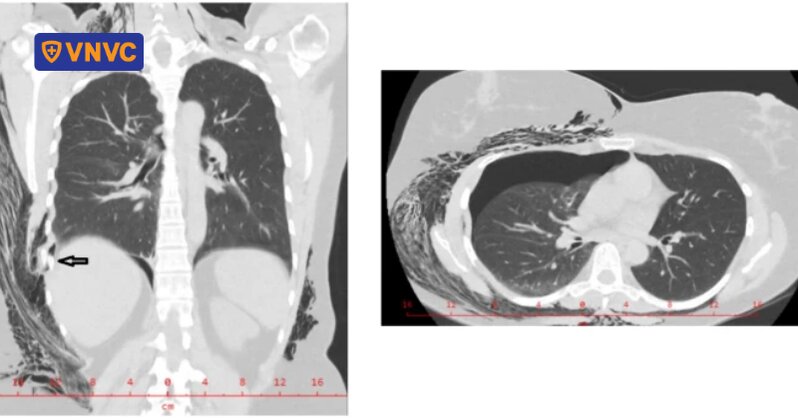

Một trường hợp khác là nữ bệnh nhân 48 tuổi, nhập viện với tình trạng đau lưng nghiêm trọng, ho khan và sưng quanh xương bả vai, lan ra cổ. Bệnh nhân được xác định bị gãy xương sườn, tràn khí màng phổi và tràn khí dưới da, xét nghiệm cho thấy nồng độ kháng thể Bordetella pertussis cao.